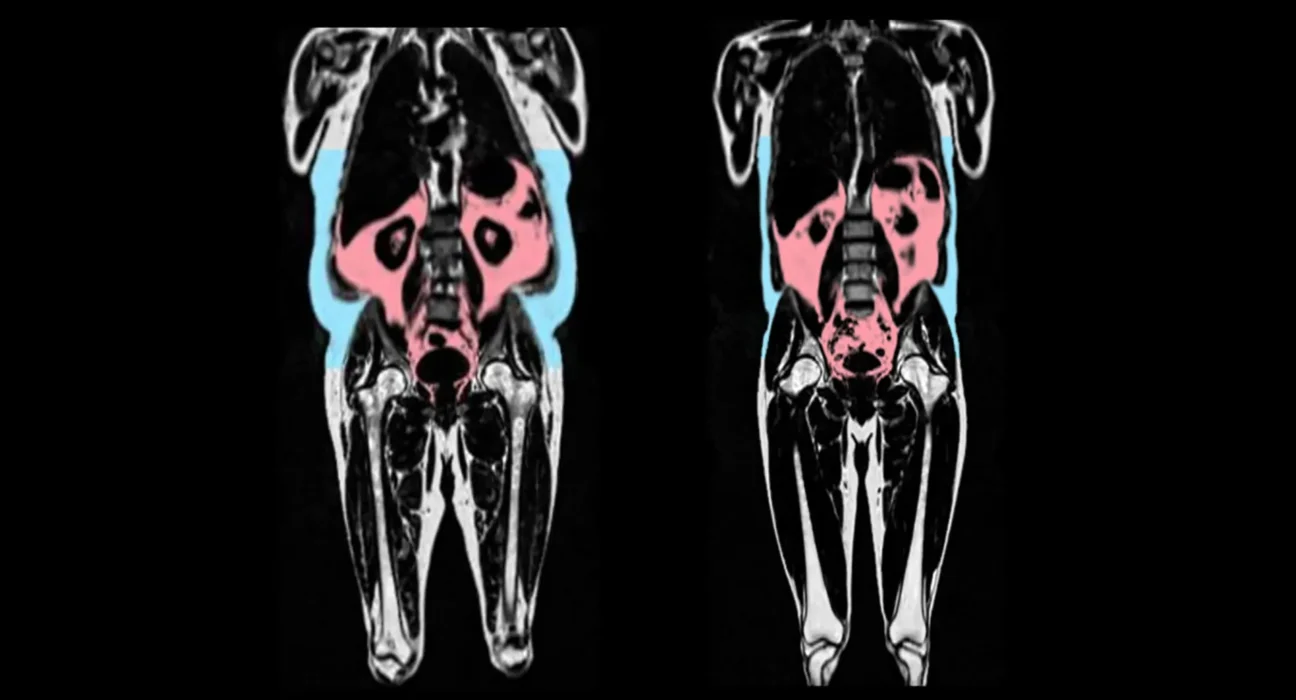

A pesquisa, liderada por cientistas do Laboratório de Ciências Médicas do Conselho de Pesquisa Médica (MRC), em Londres, Reino Unido, também encontrou diferenças entre homens e mulheres e descobriu que a gordura em torno dos quadris e das coxas poderia potencialmente retardar o envelhecimento do coração nas mulheres.

Além disso, eles descobriram diferenças entre os sexos. O padrão de distribuição de gordura do tipo masculino (gordura ao redor da barriga, frequentemente chamado de forma “maçã”) foi particularmente preditivo de envelhecimento precoce nos homens.

Em contraste, uma predisposição genética para a gordura do tipo feminino (gordura nos quadris e coxas, frequentemente chamada de forma “pera”) foi protetora contra o envelhecimento do coração nas mulheres.